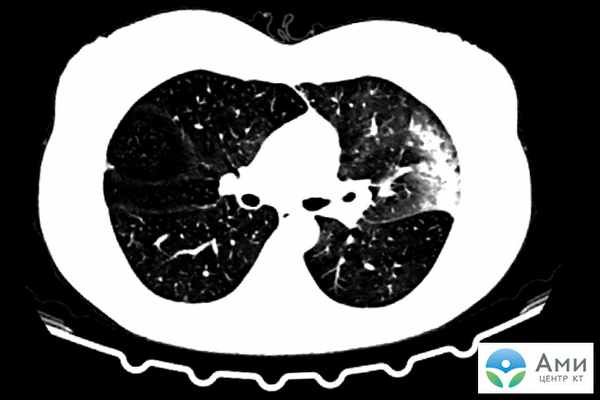

На сканах КТ ОРДС визуализируется набором специфических признаков: множественные фрагментарные участки «матового стекла» кортикальной формы с обеих сторон, увеличенная в размере легочная ткань, утолщение межальвеолярных стенок (симптом «лоскутного одеяла» или «булыжной мостовой»).